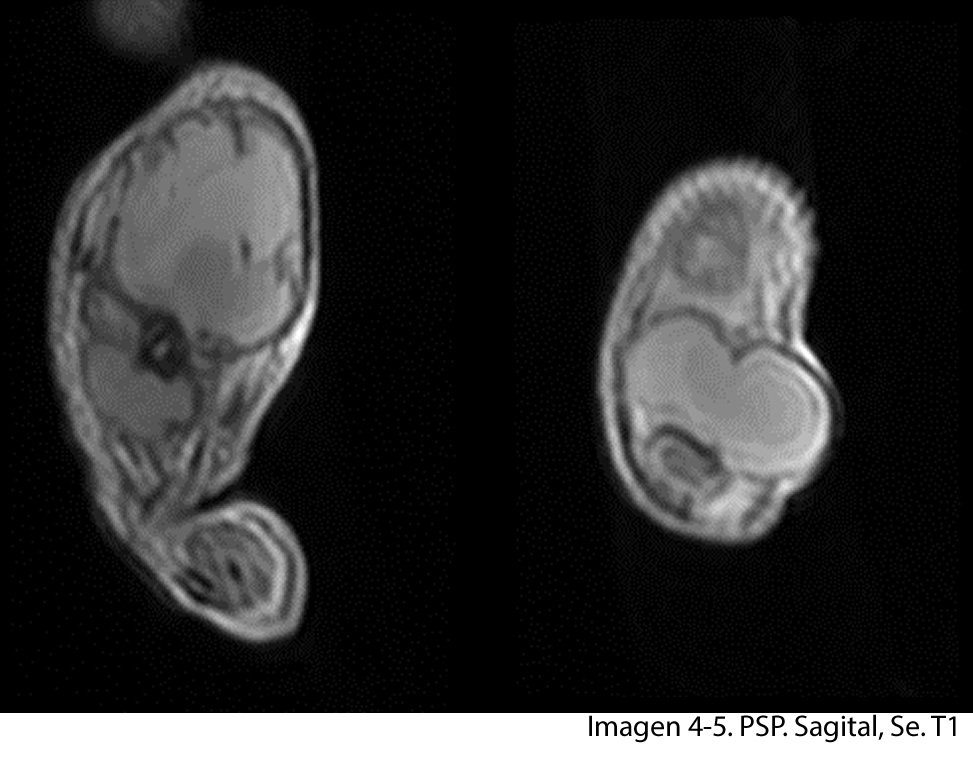

Se realiza estudio de resonancia magnética con un equipo de 1.5 tesla, se aplica protocolo de sedación, se utiliza bobina fase arrays, y se procede a adquirir un PSP, en tres planos, secuencias Se, ponderadas a T1 y T2, se administra medio de contraste por vía I.V.

A nivel del muslo izquierdo se observa una colección bilobulada, en la parte proximal se observa imagen que mide 7.05 x 7.17 cms en el tercio distal se observa imagen que mide 3 x 4.01 cms. En la ponderación T2 la lesión se vuelve hiperintensa y en la ponderación T1 con mdc la lesión se vuelve hipointensa con realce de la periferia, lo que confirma la presencia de absceso.

La diáfisis femoral proximal se ve totalmente destruida, a nivel del hombro izquierdo la cabeza del humero no se observa.